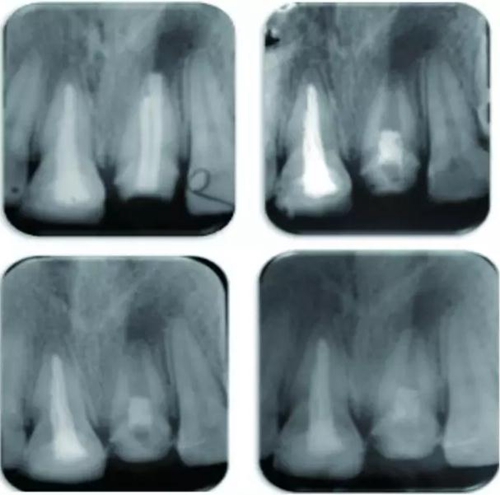

治療持續(xù)性根尖周炎,牙髓再生治療術(shù)或有效

8月13日在線發(fā)表于《牙體牙髓病學(xué)雜志》(J Endod)的兩個(gè)成功病例顯示,對(duì)于根管治療后持續(xù)性根尖周炎患牙的再治療,牙髓再生治療術(shù)或有應(yīng)用的潛能。

例為兩名年齡分別為26歲和12歲的男性患者,各有一顆恒牙(牙位分別為21與35)因患有根管治療后持續(xù)性根尖周炎而需進(jìn)行再治療。用Carvene 牙膠溶解劑和ProTaper普通旋轉(zhuǎn)式再治療根管銼去除患牙根管內(nèi)充填的牙膠,接著進(jìn)一步用旋轉(zhuǎn)再治療銼和大量次氯酸鈉對(duì)根管進(jìn)行化學(xué)機(jī)械法清理,然后用Metapaste 干燥根管。對(duì)21和35兩患牙進(jìn)行牙髓再生術(shù)治療。將根尖周的出血引入消毒后的根管內(nèi),用礦物三氧化物聚合物(MTA)填料覆蓋血塊,根管口修復(fù)材料填充。

結(jié)果為,兩患牙分別在隨訪13個(gè)月及14個(gè)月時(shí)表現(xiàn)出根尖周炎的臨床恢復(fù)體征和/或癥狀。21患牙顯示出根管變窄以及根尖部硬組織沉積而形成根尖封閉。

3.jpg

圖 21治療全過程,圖A 為治療前根尖片,圖B 為術(shù)后根尖片,圖C 顯示治療7 個(gè)月后根尖陰影縮小,圖D顯示治療后13個(gè)月根管口變窄